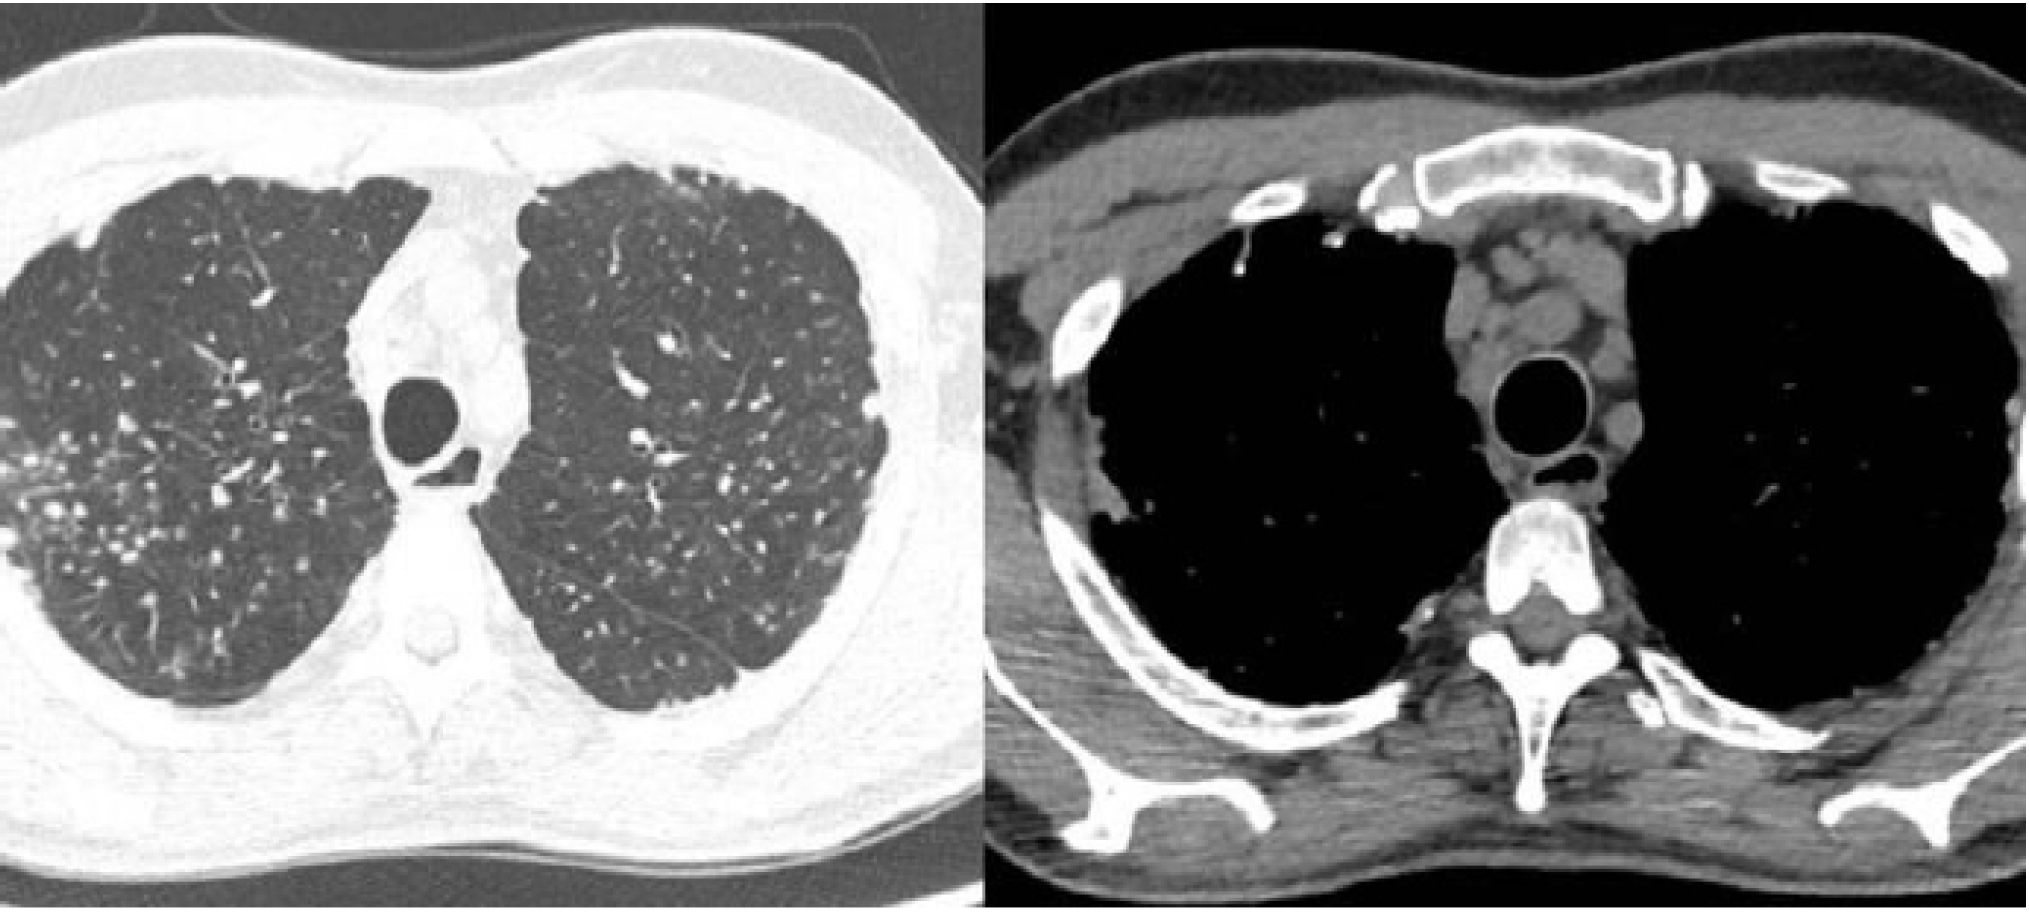

Although there were no parenchymal changes on chest computed tomography (CT), there was mediastinal lymphadenopathy and multiple pulmonary nodules, some calcified, predominantly in the upper lobes (Fig. 2). Spirometry revealed a moderate restrictive ventilatory disorder, with forced vital capacity (FVC) of 2.93 L (63%), forced expiratory volume in 1 second (FEV1) of 2.35 L (62%), and the ratio of FEV1 to FVC (FEV1/FVC) of 81 (98%), with no response to a bronchodilator. The assessment of DLCO (diffusing capacity of the lung for carbon monoxide) was not performed. The transthoracic echocardiogram showed atrial and ventricular chambers with normal volumes and thicknesses, normally functioning valves, and a pulmonary artery systolic pressure of 27 mmHg. Signs of erosive esophagitis and mild antral gastritis were also found on the endoscopic examination.

Chest computed tomography. (A) Presence of small, non-specific pulmonary nodules. (B) Increased number of lymph nodes and mediastinal lymphadenopathy.

However, the tomography did not show typical parenchymal changes associated with interstitial lung diseases related to systemic sclerosis, and it revealed diffuse mediastinal lymphadenopathy. As a result, a pulmonology evaluation was requested, especially considering the patient's significant occupational exposure to silica, which could be an important differential diagnosis. At this moment, the main hypotheses raised for the case were sarcoidosis, silicosis, or miliary tuberculosis. Given the clinical picture, a bronchoscopy with transbronchial biopsy was recommended.